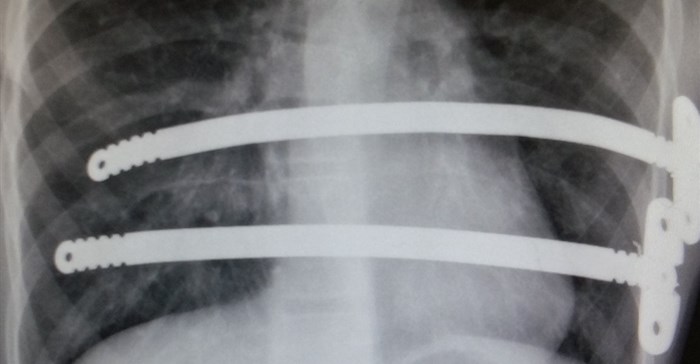

The Nuss procedure involves temporarily placing curved metal bars behind the sternum to lift it to a normal position. It has been used to correct the deformity in at least 100,000 patients around the world since it was first developed by South African-born Professor Donald Nuss, and we were greatly honoured that he travelled from the United States to attend the 2019 congress,” said Schewitz.

The intricate Nuss procedure usually takes approximately two hours to complete, and is internationally regarded as the gold standard in the treatment of appropriate patients with more serious sunken chest.